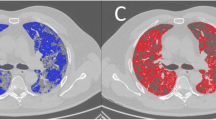

According to the inclusion criteria, 201 cancer patients with COVID-19, including 36 variables indices, were included in the analysis. The top eight indices (albumin, lactate dehydrogenase, cystatin C, neutrophil count, creatine kinase isoenzyme, red blood cell distribution width, D-dimer and chest computed tomography) for predicting the occurrence of ACI in cancer patients with COVID-19 infection were included in the RF model. The model achieved an area under curve (AUC) of 0.940, an accuracy of 0.866, a sensitivity of 0.750 and a specificity of 0.900. The calibration curve and decision curve analysis showed good calibration and clinical practicability. SHAP results demonstrated that albumin was the most important index for predicting the occurrence of ACI. LIME results showed that the model could predict the probability of ACI in each cancer patient infected with COVID-19 individually.